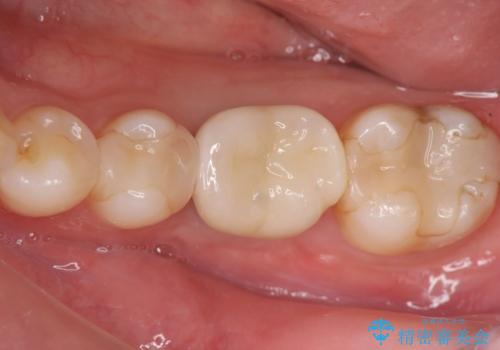

欠損部のインプラント補綴

- 失った奥歯にインプラント治療を受けたい、と希望され来院されました。

前後の歯を削らずに機能回復できるインプラントを用いて審美生、咬合機能の回復を計画します。

- 44万円(インプラント・チタンカスタムアバットメント・ジルコニアクラウン・仮歯)費用は治療当時の料金となります

痛みや腫れもほとんどなくインプラント治療を終えられ、しっかり噛むことができるようになった。と治療結果に満足いただくことができました。